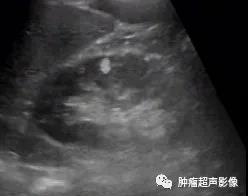

超声检查发现双肾多发AML,尤其是肿瘤数目较多、瘤体较大、肾脏轮廓不清时要想到TSC的可能,并询问相关病史,并观察面部、建议颅脑CT检查等。肾囊肿在TSC中也较常见,是该病临床诊断的次要指征。肝AML在超声上与血管瘤表现类似,均表现为大小不等圆形或椭圆形偏强回声团块,肝AML含有脂肪成分,回声比血管瘤回声更强一些,结合TSC病史,肝脏多发偏强回声占位应首先考虑为AML。

体检发现双肾多发错构瘤,双肾密集分布,考虑结节性硬化症表现,建议头颅检查(病例由江口县人民医院胡海英医师提供)

女,61,因肾肿瘤入院治疗,超声及CT示两肾多发错构瘤,建议头颅检查。